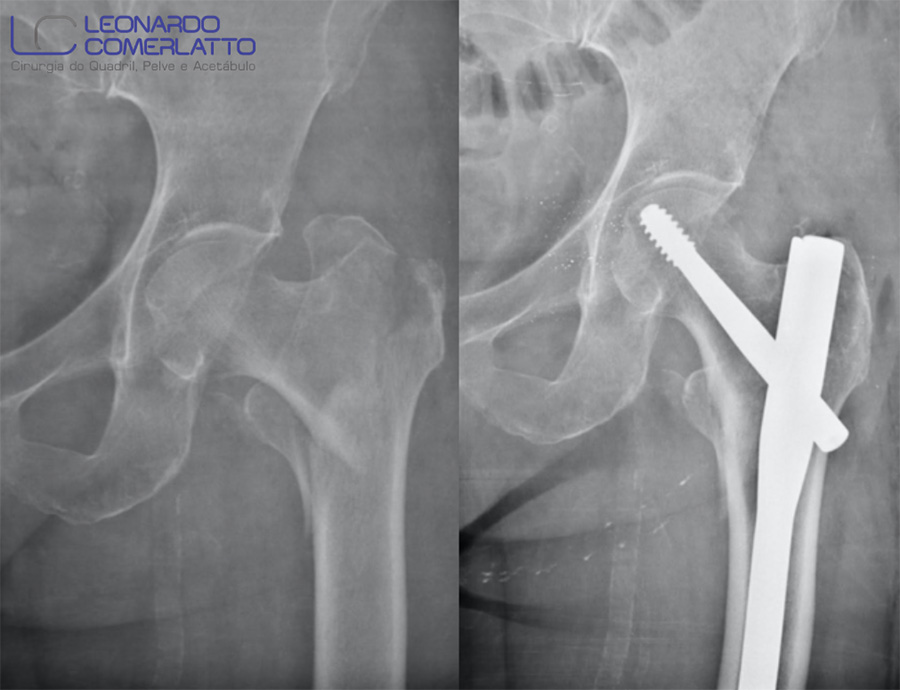

- Radiografia pós-operatória de uma paciente idosa que sofreu queda domiciliar resultando em uma fratura trocantérica do fêmur. O procedimento é realizado de forma minimamente invasiva e possibilita uma reabilitação precoce.

- Haste cefalomedular, um dos implantes mais utilizados no tratamento de fraturas que acometem a região proximal do fêmur.